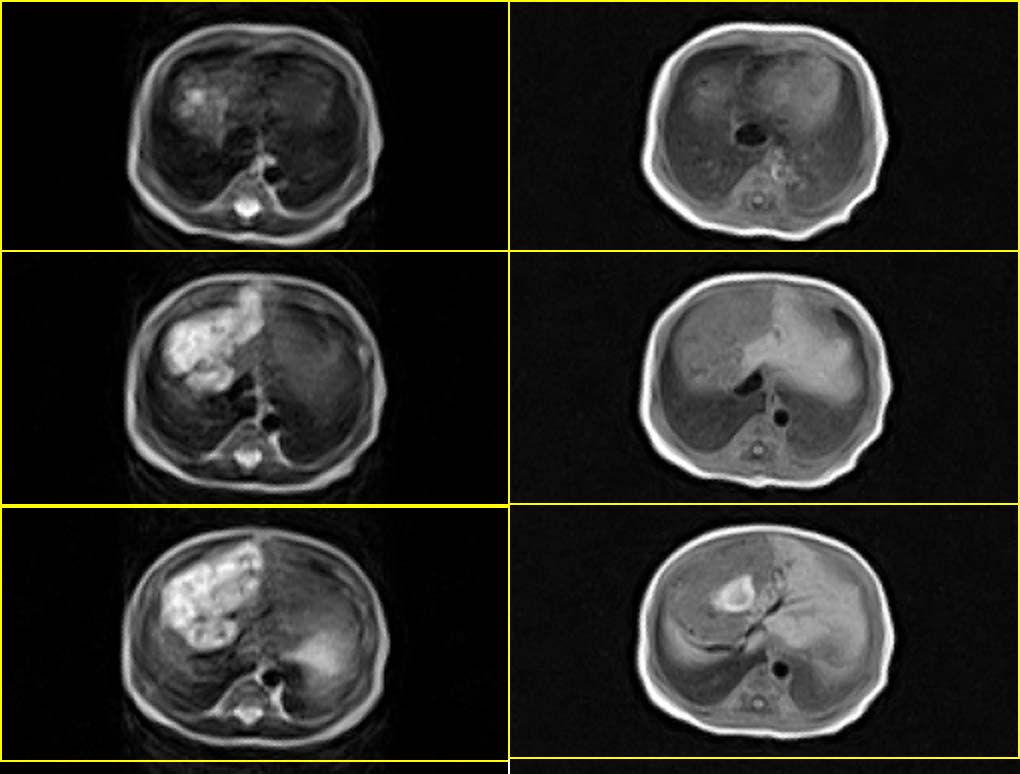

患者男性,3天.

因生育前b超发现肝脏占位,怀疑血管瘤而行mr检查.

请分析您的诊断是否与b超诊断相同?